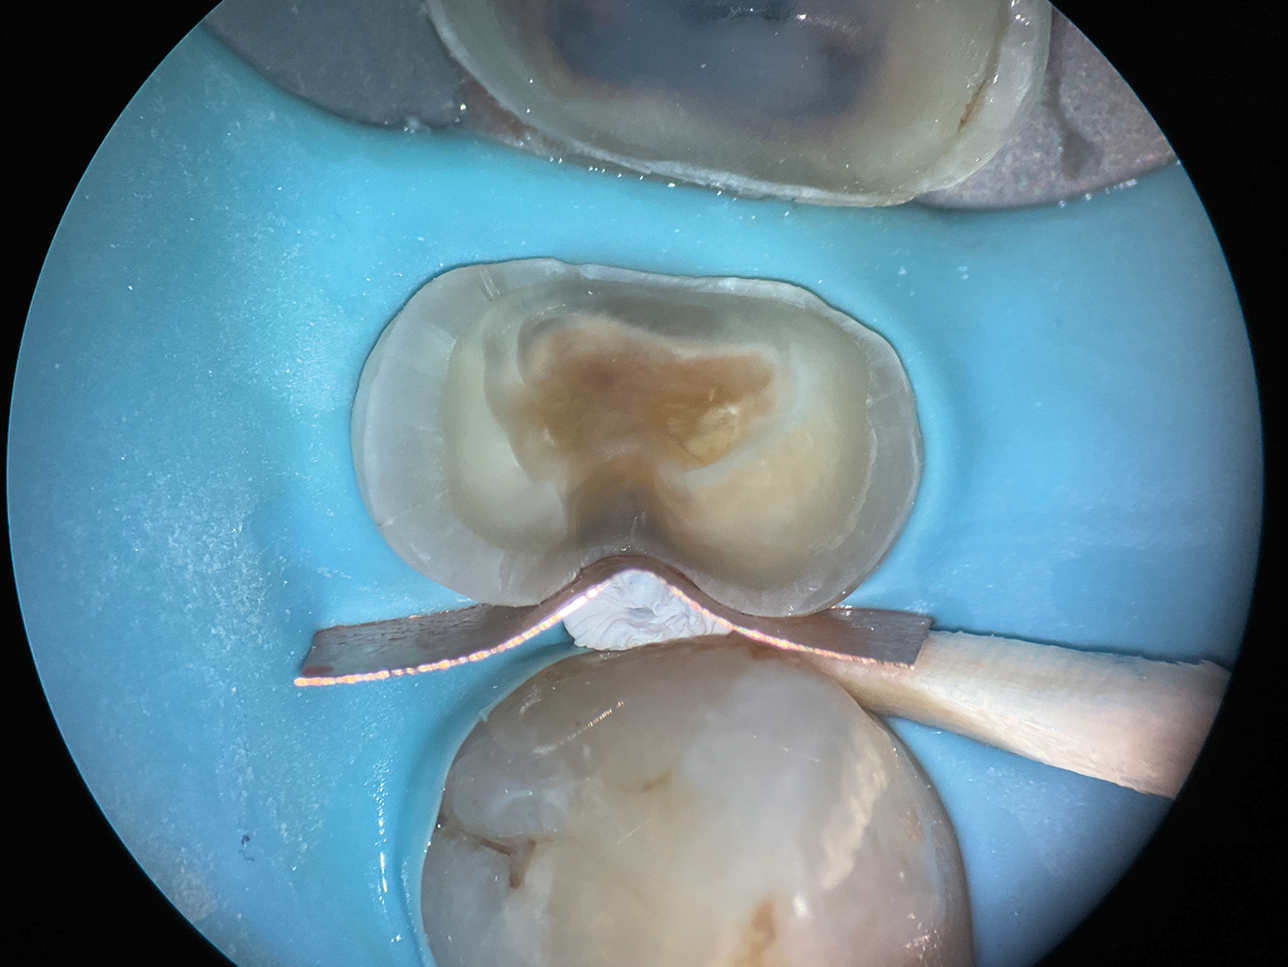

The root surfaces of maxillary molars present unique challenges due to their distinct anatomical concavities. On the mesial surface of the maxillary first molar, a pronounced concavity extends toward the furcation (Figure 7), whereas the distal surface features a broad and shallow depression that extends coronally to the cementoenamel junction. These concavities can pose significant difficulty in restorative procedures, particularly for deep Class II cavities, where their complex morphology complicates the adaptation of a single matrix (Figure 8).

To overcome these challenges, a matrix-in-matrix approach provides a reliable solution (Figure 9). The technique involves placing a circumferential matrix as a base, followed by a precision-shaped copper band with a thickness of 2 to 3 mil. The copper band conforms to the intricate contours of the concavities and serves as an auxiliary support. A liquid dam material is placed between the two matrices for added stability.

(8.) Close-up occlusal view of a maxillary first molar after the removal of deep subgingival caries, where despite rubber dam isolation, infiltration of blood and saliva into the cavity has occurred.

Figure 8

(9.) Close-up occlusal view of the maxillary first molar prepared for a matrix-in-matrix technique with a circumferential matrix supported by a 3-mil copper band inside for proper adaptation to the margin’s concave and convex areas. Note the addition of a liquid dam material placed between the two matrices for added stability.

Figure 9